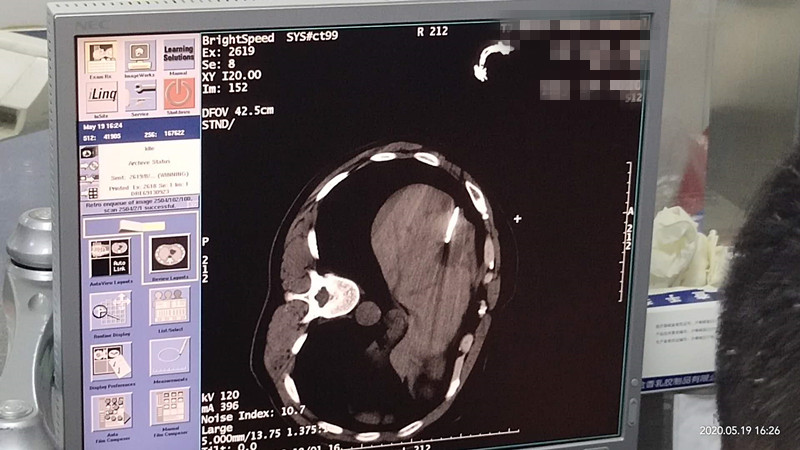

47岁腹腔氩氦刀冷冻消融

发布人:美国氩氦刀技术官方网站    发布时间:2020/5/22 14:53:58